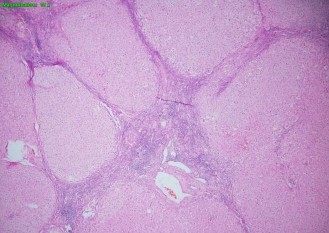

Hình 2.11. Tổn thương gan 5/6 theo Ishak (BN N18-0396611)